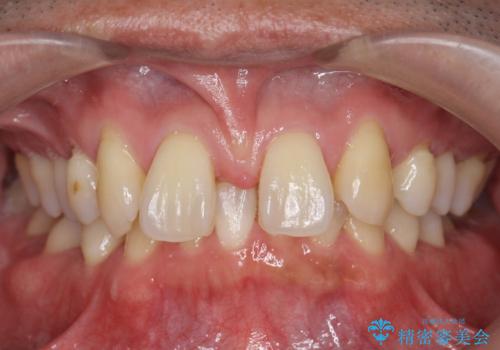

- 前歯部のすきっぱと歯並びが気になるので診て欲しいといらっしゃった方の症例です。

全顎矯正は御希望されなかったため、上顎前歯部のみの部分矯正とオールセラミッククラウンによる補綴を行いました。